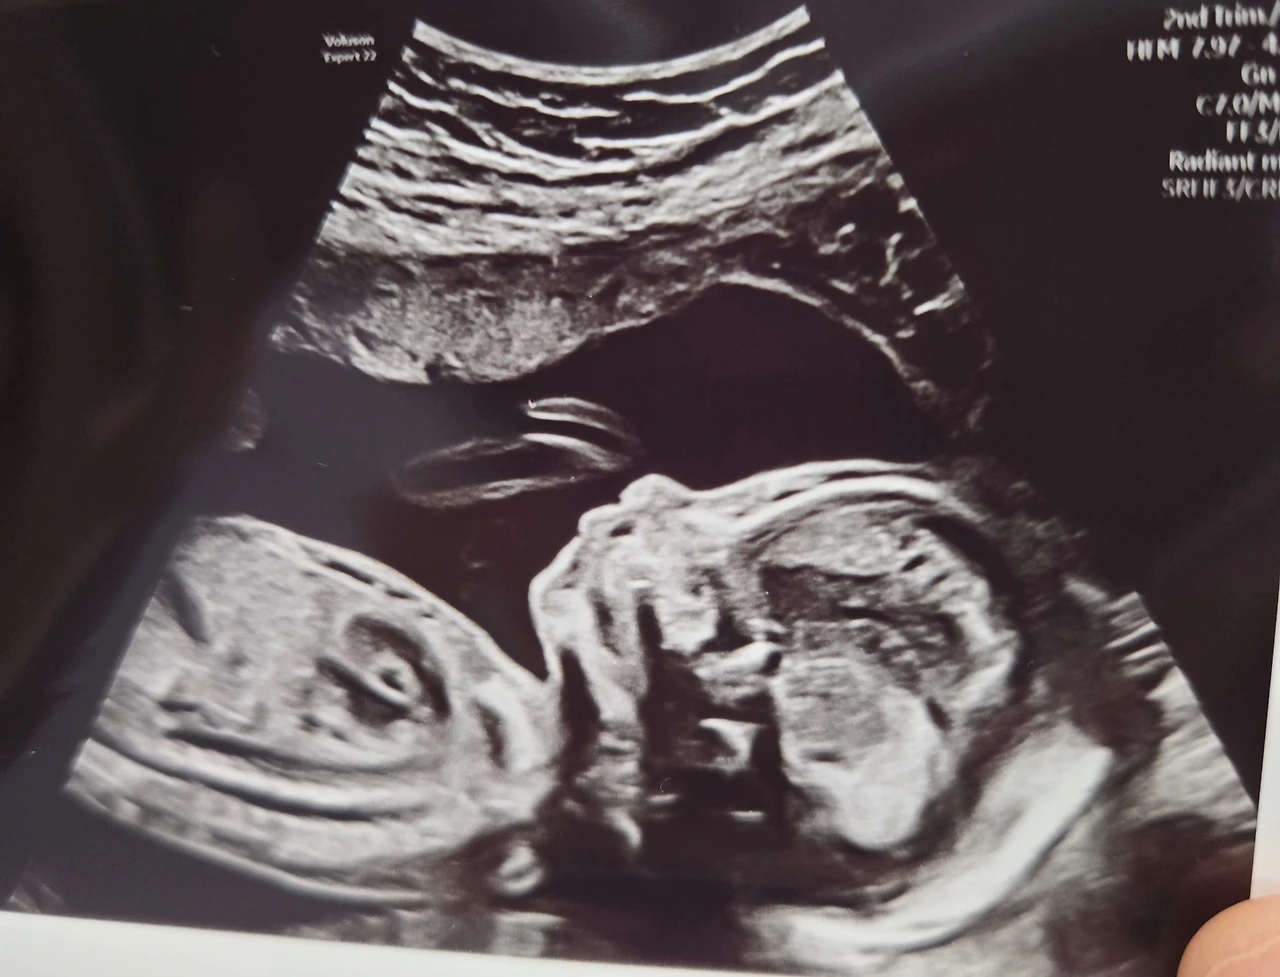

오늘은 21주차 정밀초음파를 보는 날이었습니다. 오전 7시45분 예약이라 일찍 자야하는데, 걱정이 되어 새벽2시에 잠들어 6시에 자다깨다 일어났답니다. 아직 태동이 없다보니 아가가 잘 있을까? 괜스레 배를 문지르기도 하고요.

그리고 오늘! 정밀 초음파를 보고 왔습니다.

콧대도 보고, 입술을 뻐끔거리는 것도 보고, 아이가 오전부터 초음파라 심술이 난건지 손으로 귀를 막기도 하고 발로 뻥뻥 차더라고요. 정말 신기한 경험이었습니다. 초음파는 머리부터 발끝까지 보느라 3-40분이 걸렸어요.

애기 심장에 하얀게 보인다고요?

의사 선생님께서 웃으시면서 밝게 들어오시길래, 당연히 아무이슈없어요! 라고 1차 초음파때처럼 들을 줄 알았는데...갑자기 선생님께서 흰 색 종이를 펼치시더니 심장 그림을 그리시기 시작했습니다... 눈 앞이 하얘지고 남편이랑 저랑 순간 멍-EIF (Echogenic Intracardiac Focus, 심장 내 고에코점) 심장 미세석회가 있다는 소견이었어요.

영어가 워낙 빠르신데다가 당황하다보니 잘 들리지 않더라고요. 심장에 구멍인건가요..? 라면서 거의 패닉에 빠졌습니다. 심장미세석회(EIF):초음파상 심장 안에 밝게(하얗게) 보이는 작은 점. 주로 좌심실(Left ventricle) 안쪽에서 관찰되며,심장 판막이나 근육에 칼슘이 살짝 침착된 것처럼 보인다. 아주 흔하진 않으나, 주로 아시아인 태아에서는 10% 이상까지도 보인다. (특히 남자아이)

의사 선생님이 영어가 좀 빠르셔서, 저희부부는 처음에 그려주신 그림만 보고 심장에 구멍이 난 줄 알고 식겁했습니다. 설명을 들어보니 칼슘이라고 하시더라고요? (석회) 1개 있었습니다. 저희가 표정이 너무 사색이 되었었나봐요. 빠르게 안심을 시켜주시면서, 매일 하루에 1명 씩은 보는 증상이다 라고 하셨어요. 심장미세석회의 경우 심장의 구조적 이상이 아니기 때문에 심장 기능에는 전혀 이상이 없다라고 하셨어요. 그냥 피부에 있는 birthmark처럼 생각하라고 하시더라고요. 다만 과거에는 다운증후군 아이들 중 10-15%정도가 저런 심장의 하얀 점을 가지고 태어났기에, 다운증후군의 소견 중 하나(softmark)로 여겨졌다고 합니다. 하지만 저는 NIPT 염색체 검사 저위험군이었기에 걱정하지 말라고 하셨어요.